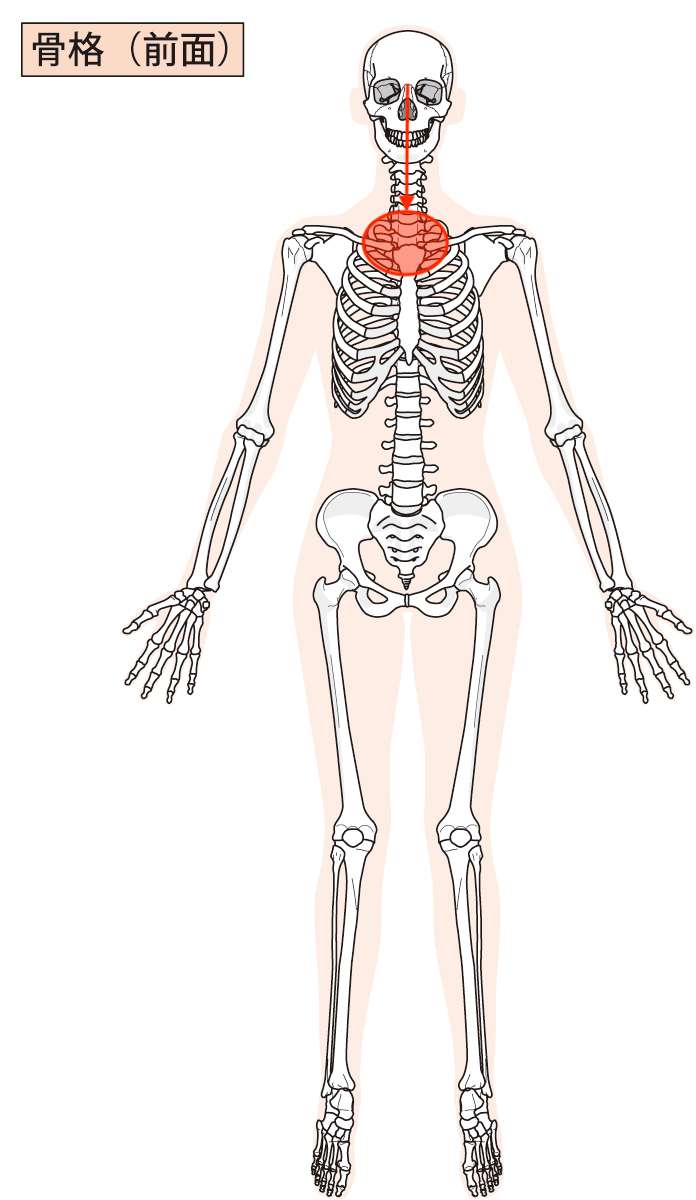

図で言うとこんな感じです。

一枚目が前から見た図と、二枚目が後ろから見た図で表しています。

図をご覧いただくと、当院にご相談くださった方の場合、赤丸の位置に痛みを感じており、その部分が痛く、また背骨の動きが制限されていました。

そして、赤の矢印が確認できるかと思いますが、その矢印の方向が赤丸を指していることがわかると思います。

この赤の矢印の方向に向かって張力(引っ張られる力)が加わっており、目の付近が赤丸の方向へ引っ張られている様子を表しています。

こんなふうにして目の奥、目の神経系や目の血管系を含めた組織が持続的に引っ張られるようなストレスを受けると、「目の痛みや目のかすみ」などの目の症状を感じることになります。

今回ご紹介させていただいた方も同じで、そういった引っ張られるようなストレスがかかることにより、目に負担となり、「目の奥が痛い」という症状の出現につながったのではないか?ということが考えられました。